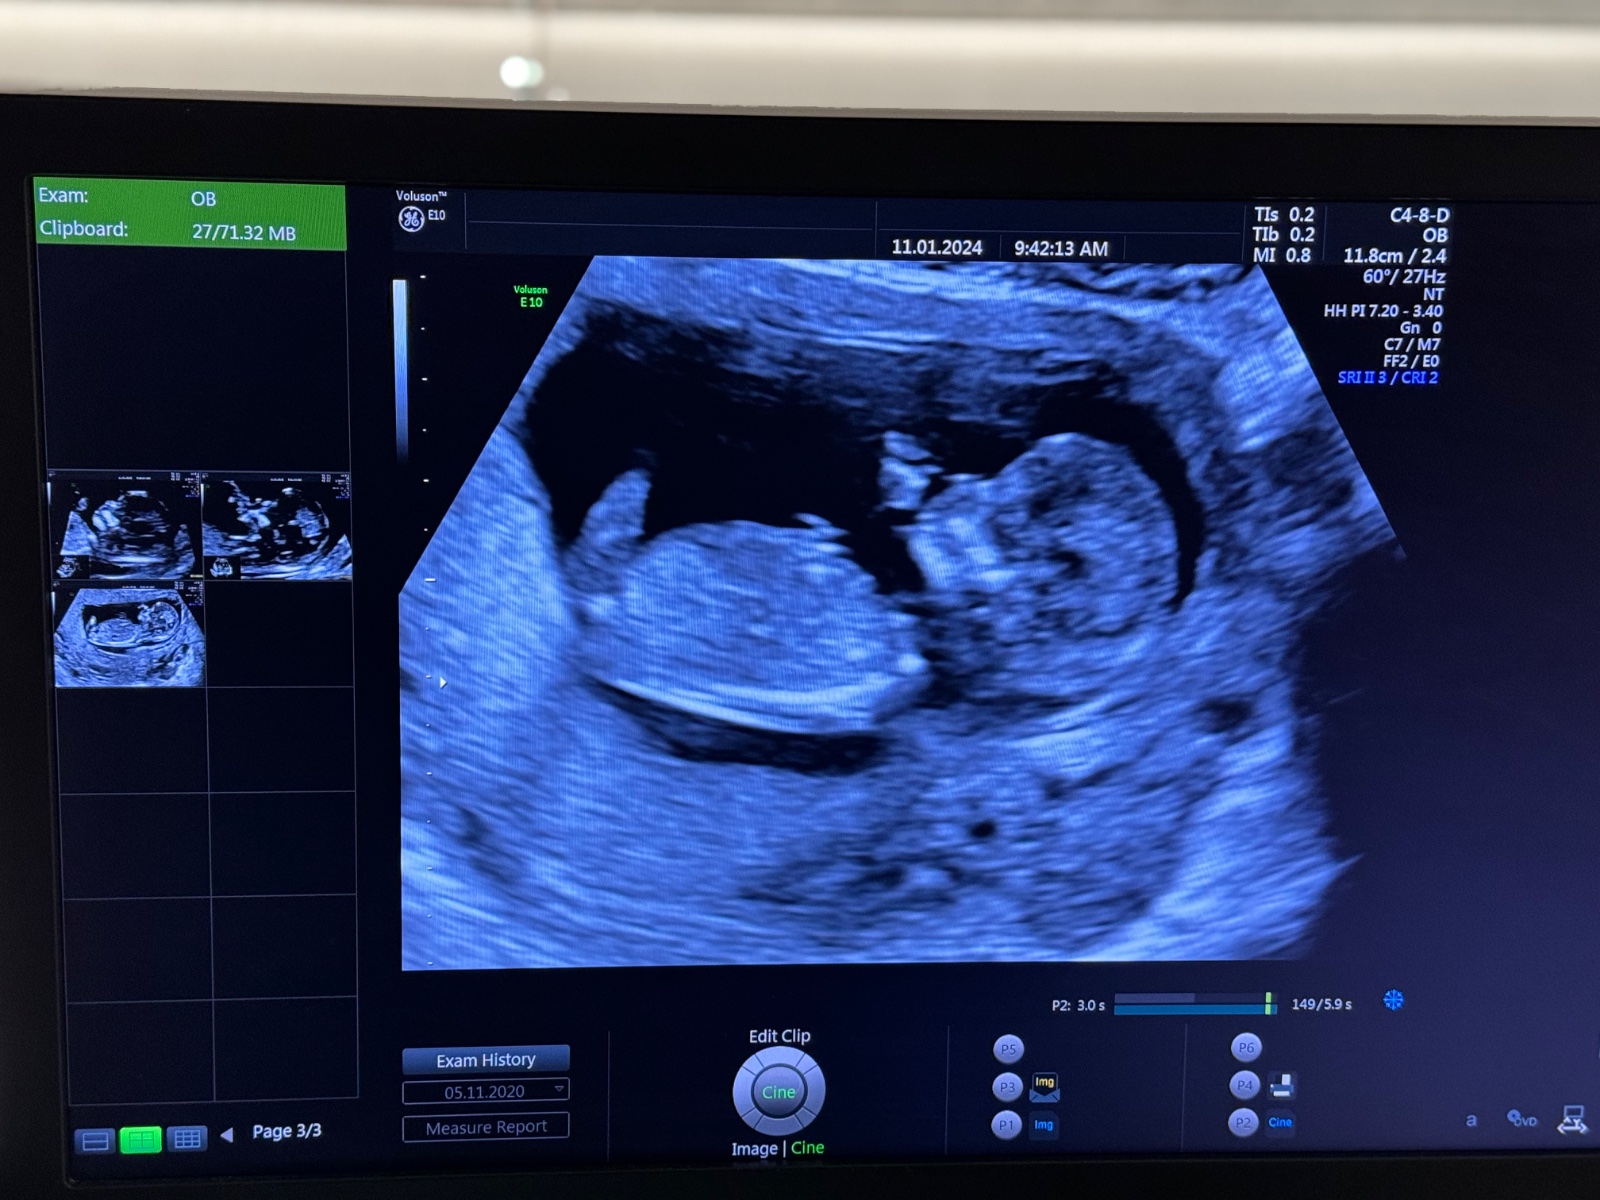

Pokud jsem správně pochopila, pokud je na ultrazvuku vidět výběžek, který směřuje nahoru, pak je to chlapec, pokud je ve vodorovném směru s tělem, pak je to pravděpodobně holčička.

Já podle svého už však nevím, zda se jedná o tento výběžek nebo jestli je to třeba nožička... :D Nemáte někdo zkušenost? 🙂 Určitě nečekám diagnózu, jen by mě zajímala Vaše zkušenost a zda jste na svém ultrazvuku neviděly třeba něco podobného. 🙂

Já bych podle toho svého tipla, ze by to mohla být holčička, ale třeba je to jen mé vymodlené přání. :D

Jsem nedočkavá, až se to u svého doktora dozvím 😍 můj screening pro zajímavost v příloze, máte tip? Za

Dobrý den, oživuji diskuzi ❤️ 11tt, je to jen screenshot z videa které jsem si natočila na mobil, tak bůh ví, zda jsem to cvakla v dobrou chvíli a není to klamavé 😄 Co myslíte? Do prenatalu jdeme až 6.11. a já mám pocit že prasknu nedočkavostí, jsem zvědavec hrozný 🙈 Toť otázka - pohlavní hrbolek, nebo jsou to kulky, nebo konec kostrče? Co myslíte, jen tak pro srandu? Přáli bychom si holku, ale kdyz jsem videla prvni pohyby na UTZ v 11+1, tak jsem si uvědomila že ať bude co bude, budu mimi milovat uplne stejne bez rozdílu ❤️ Je to mazec!!